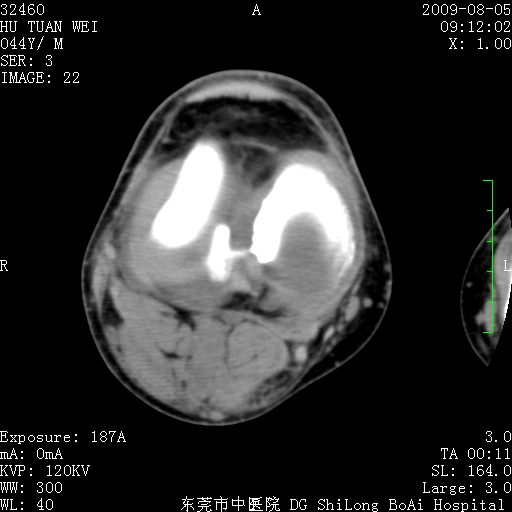

中年男性,膝韧带损伤术前检查!其他病史不清粗,不是我接手病人、且出院了!

1、股骨下段囊状膨胀性病变,边缘硬化明显,内多个残留骨棘呈多房型改变,囊腔密度较高无钙化,膝关节滑膜囊增厚,密度增高,关节腔少量积液。考虑:邻关节囊肿、退变性囊肿(软骨下囊肿)、着色性绒毛结节性滑膜炎、abc、骨巨、良性纤维组织细胞瘤等鉴。虽然年龄偏大,部位于骨端,但有外伤史,本人还是倾向于动脉瘤样骨囊肿(abc)可能性大。邻关节囊肿及软骨下囊肿次之考虑。

2、胫骨髁间棘撕脱骨折,交叉韧带损伤可能;

3、关节退行性改变。

病理结果:色素沉着绒毛结节性滑膜炎

感谢反馈病理结果!本病为慢性关节病变。以关节滑膜高度增生、绒毛结节形成伴含铁血黄素趁着为特点。病因:有炎症、肿瘤、外伤关节出血、代谢障碍、变态反应及感染等学说。增强扫描呈关节腔内单个或多个强化的软组织结节影或滑膜不规则增厚伴关节积液为本病的特征性表现。